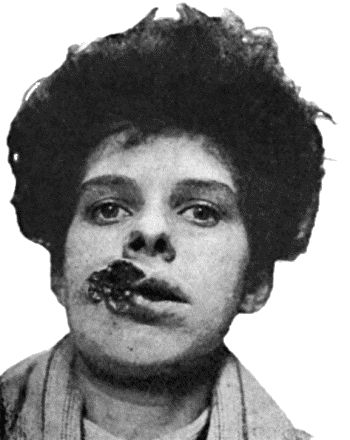

| 23. | Cancrum Oris | 103 |

| 41. | Ulceration in inherited Syphilis | 170 |